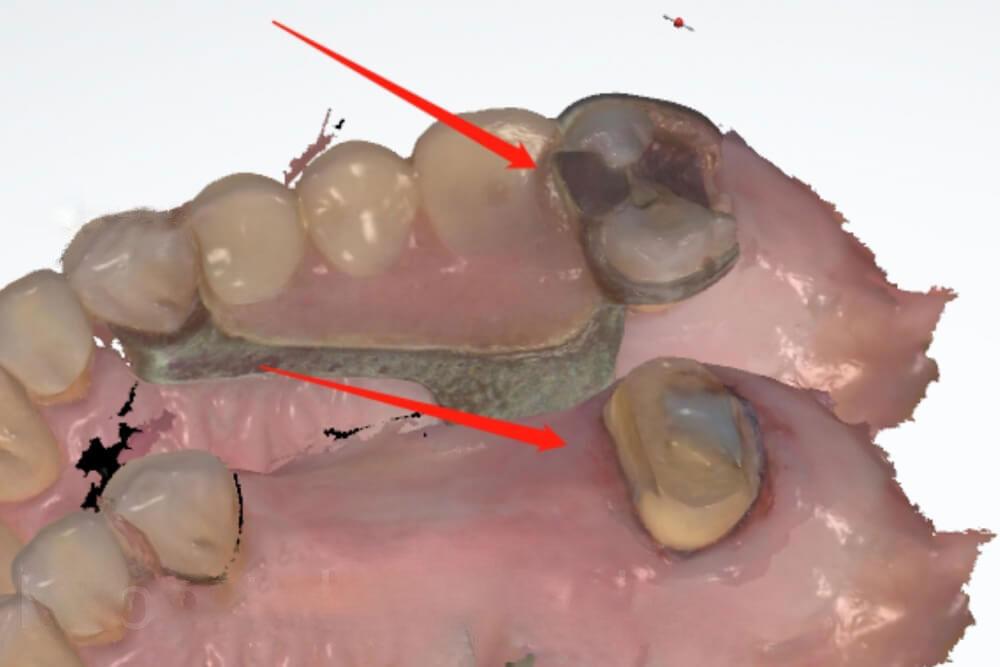

Let’s see a real case example. Our dental clinic sent 2 scans to us. One scan was with the partial in the patient’s mouth, while another scan was with a prepared tooth. The dentist asked us to 100% copy the patient’s original molar tooth, so the crown could fit to the her existing partial. Unfortunately, we could not help the dentist fit to partial, because the partial covered the natural tooth in the scan. In this case, we could only make a crown with our experience, so the dentist would have to make adjustments.

Now let’s look at another example. In the first scan (the left picture), the dentist took off the partial, and scanned the natural tooth. In the second scan, the dentist prepared the natural tooth, and scanned the prepared tooth. That was the correct way for Fit to partial cases.